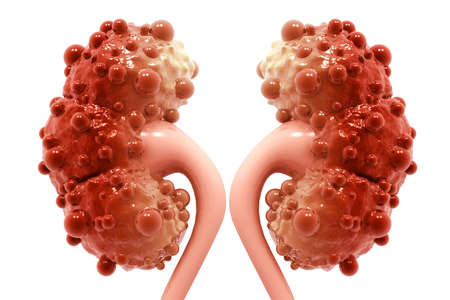

Kidney disease. 3d illustration

3d rendered medically accurate illustration of diseased kidneys